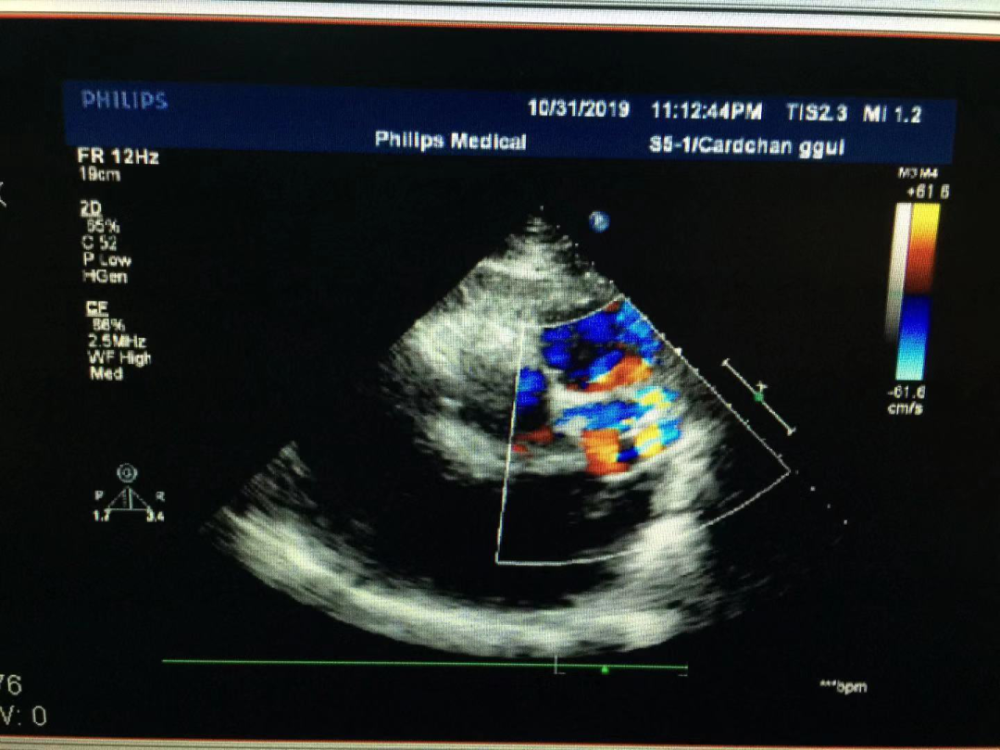

a:彩色多普勒超声心动图显示左心室扩大,舒张期大量主动脉瓣反流;b

图1 bav患者主动脉短轴切面:左冠瓣与右冠瓣融合钙化(箭头)